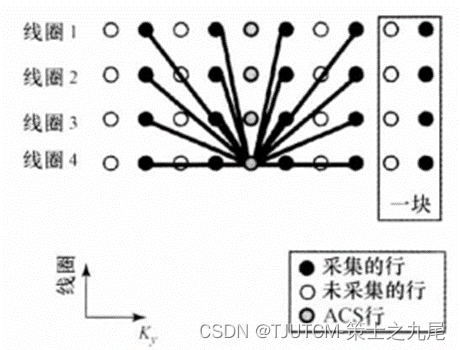

与线圈阵列中线圈数目相等阶次的谐波有时难以构建出来,而推广SMASH可用靠近Km+1行的第一个负谐波来代替靠近Km行的第二个正谐波。因合成较低谐波,比合成高谐波更准确。

另一个推广是 块重建,用多测量行合成缺失的谐波行Km+pΔK。这种推广提高了拟合精度,特别是对于难以用线圈灵敏度线性组合来逼近的复指数函数的线圈排列。构建缺失的K空间行所用测量行越多,图像质量越好,代价是重建速度越慢。

(a)图为可用于SMASH的四线圈阵列

(b)图为线圈灵敏度

©图为线圈灵敏度之和(1)

(d)、(e)、(f)为灵敏度组合

对于SMASH最佳线圈几何或许是沿一直线放置的线圈阵列,虽然对于任意线圈几何SMASH也能产生高质量图像。并行成像也可应用到3D扫描的第二个相位编码。在高场SNR很高,并行成像最有用,最成功的应用之一是对比剂增强的MRA。降低扫描时间对于捕捉团注通过的峰值,缩短屏住呼吸时间是有利的。用SSFP梯度回波序列(比如True FISP)对心脏扫描给出足够的SNR允许加速因子R>=2。这导致较短的屏住呼吸时间、较好的空间分辨或时间分辨。